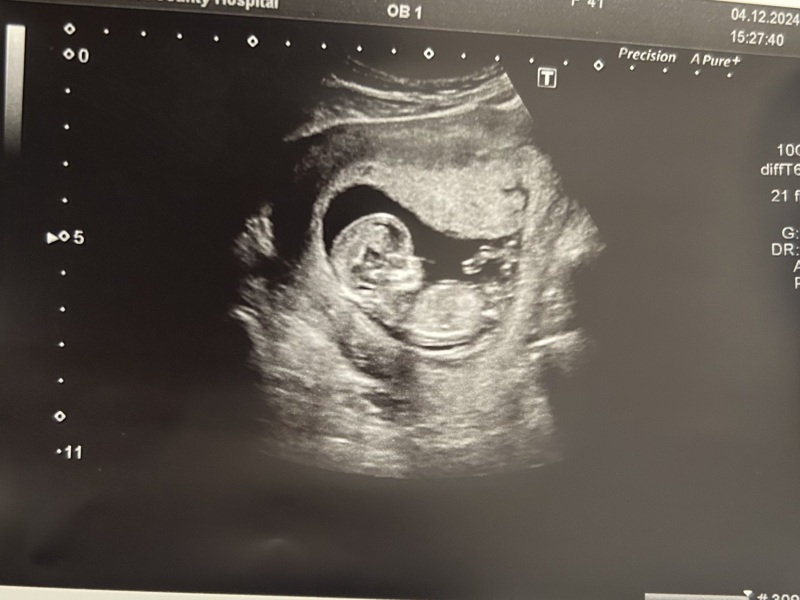

We had our dating scan today and all is well! My due date has been moved back to 15th June, so I am now 12+3. So relieved the little one is ok - now we can really start to get excited! Anyone have any guesses on the sex?

@BertLiv i vote girl off skull theory 🩷

Congrats @BertLiv, lovely scan pic, I won't hazard a guess as don't know enough 😆

Congrats ladies! I was measuring right on time at 12+4 and was very very relieved. We aren’t sure what this one is looking like as skull is saying boy but spine is straight so girl? Maybe someone can do it better than me?

LacedBouquet · 04/12/2024 18:55

I vote boy!